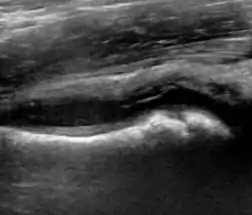

During childhood, ultrasound is a quick method to assess hip pain and quite often may be used to avoid use of irradiating techniques, such as radiography or CT. Ultrasound allows evaluation of joint effusion, synovial thickening and neovascularity, the bone/cartilage contour, and the femoral head-neck alignment. Although sonography is extremely sensitive in detecting increased synovial fluid, it is nonspecific and cannot be used with accuracy to determine the type of fluid. Transient synovitis of the hip, despite being the most frequent cause of pain in children between 3 and 10 years, remains a diagnosis of exclusion. It usually shows anechoic fluid, but echogenic fluid can also be found. The effusion is considered pathologic when it is measured at >2 mm in thickness. The differential diagnosis is wide, including osteomyelitis, septic arthritis, primary or metastatic lesions, LCPD, and SCFE. Discrimination from septic arthritis is challenging, often requiring joint aspiration. In septic arthritis, US is able to demonstrate a hip joint effusion, synovial thickening, and cartilage damage, although the appearances are nonspecific.[1]

Figure 12:

- Normal ultrasound appearance of the femoral head-neck junction.

- Joint effusion in transient synovitis of the hip.

- Flattening of the femoral head in a patient with Perthes disease.

- Step in the femoral head-neck junction in a patient with SCFE.